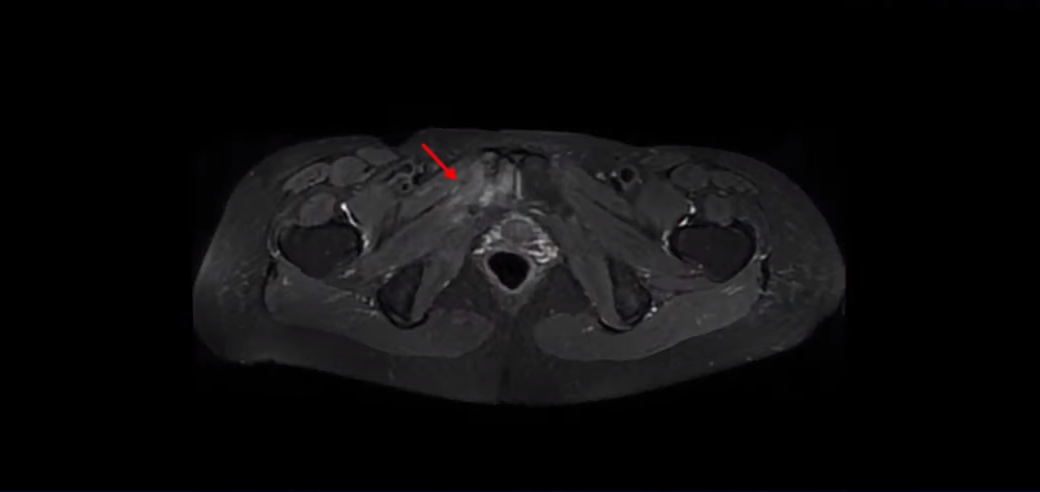

이 환자분은 아주 심하게 넘어지면서 엉덩이 근육이 파열되고 고관절에 미세 골절이 발생한 분입니다.

근육이 파열되어서 극심한 통증과 함께 일어서기도 어렵고 걷기도 어려워서 심지어 침대에 올라가기도 어려운 상태였습니다. 소염 진통 주사를 몇 번 맞았지만 전혀 효과가 없었습니다.

상태가 안 좋아 초음파를 했는데 엉덩이 근육이 심하게 파열돼 있고 인대도 많이 손상됐으며, Ct도 찍었는데 치골과 비구가 미세골절 상태였습니다. 정형외과 세 군데에서는 6개월 정도 아주 오래 걸리는 부위라고 무조건 집에만 있으라고 얘기했어요. 그리고 모든 선생님들이 염증이 지독하다 해서 소염진통제 3대를 맞았지만 전혀 나아지질 않고 열이 나면서 더 아파지고 쇠망치로 맞은 느낌과 화끈거림이 계속됐어요.